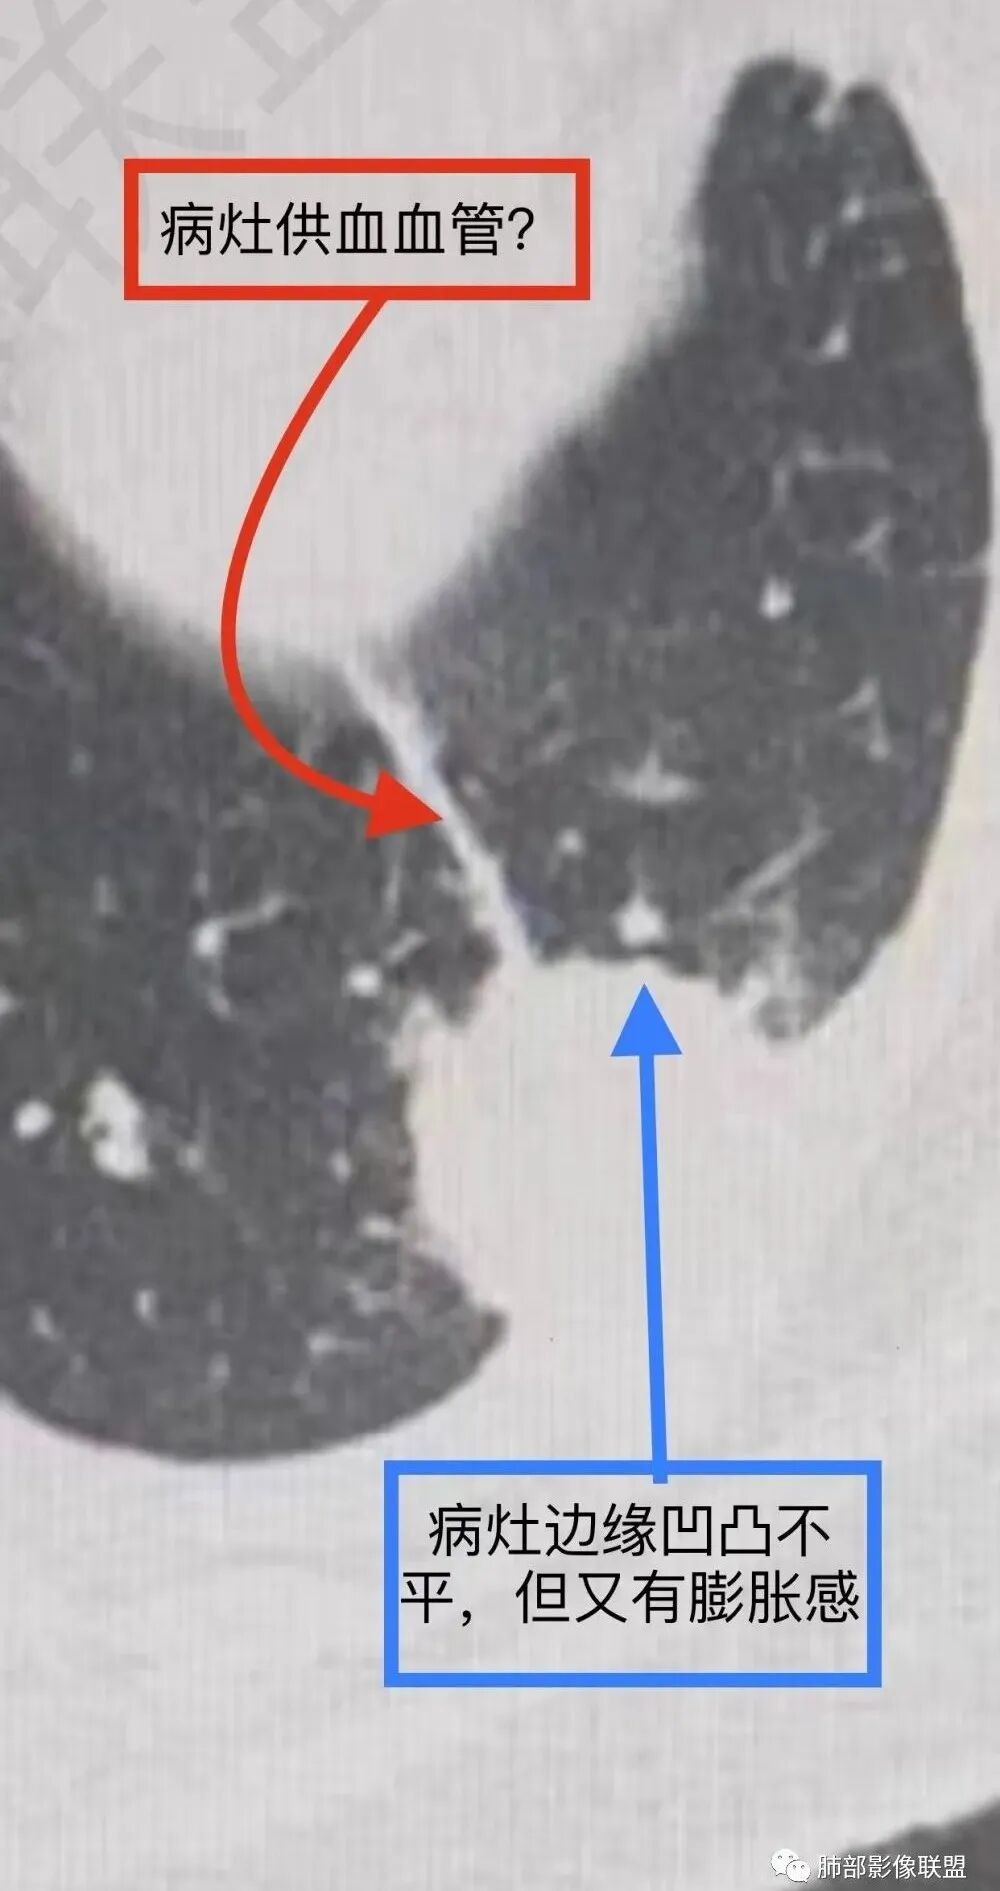

谢加平:老年女性,慢性咳嗽,咳白痰史,左肺下叶后基底段胸膜下肿块,类圆形,边界清膨隆,密度不均匀,低强化及小灶性坏死,坏死轮廊不清,胸膜下栽赃明显,左侧胸腔少量积液,向胸壁肌侵犯,另肿块近心侧见支指套征,粘液低密度,支持恶性,粘液腺Ca,经皮肺穿刺活检明确诊断。

袁媛:左肺下叶胸膜下球形肿块,宽基底连于胸膜下,胸膜栽赃,边缘膨隆,有血管供应,增强有强化,考虑腺癌。

人生海海:左肺下叶不规则形软组织密度影,膨隆生长,边缘清楚,分叶,棘突征,支气管截断,血管纠集,病灶轻度强化、内多发坏死,左侧少量胸腔积液,考虑粘液腺癌,鉴别肺脓肿。

赖晓宇:膨隆,浅分叶,支气管截断,内部坏死边界不清,胸膜受累,胸腔积液,考虑恶性。

良孑:左肺下叶胸膜下结节,可见晕征及软毛刺,边缘有锯齿状浅分叶,其内坏死边界不清,均匀性低强化,局部层面边缘可见平直及u型凹陷,胸膜糊墙并少量积液,慢性病史急性发作,炎性标志升高,首选炎性肉芽肿性病变,0P并脓肿,高龄,有锯齿状浅分叶腺癌也难以除外。

放射线:左肺下叶后基底段胸膜下肿块,边缘膨隆,密度不均匀,内见低密度坏死,胸膜栽赃,左侧胸腔少量积液,考虑恶性,腺癌?鉴别放线菌,OP伴脓肿。

南边:今天的病例肺内部分基本都是炎性特点,问题就在于胸膜。

糊墙:肺内病灶不侵犯壁层胸膜或以外,与壁层胸膜相对而言分界清楚。

栽赃:病灶侵入壁层胸膜及胸膜外脂肪间隙、胸壁其他结构等,相对在病灶中央区域,与胸膜分界不清。

南边:看肺内病灶与胸膜分界清,增强后强化不一致,需要综合分析。

这是糊墙。

这就栽赃。都突到外面去了。